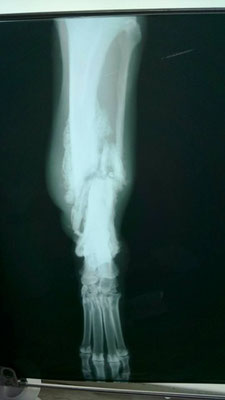

Ein alter Bruch, der sehr schlecht zusammengeheilt war, hat sein linkes Hinterbein um zwei bis drei Zentimeter verkürzt. Vermutlich wurde er angefahren oder durch einen anderen Unfall

verletzt.

Wenn alles ausgeheilt ist, wird entschieden, ob der Bruch noch einmal operativ behandelt werden muss oder der Hund mit seinem verkürztem Bein ohne Folgeschäden leben kann.

Dann wird nach weiteren Untersuchungen entschieden, welche Optionen man zur Behandlung seines verkürzten Hinterbeines hat und ob eine Operation notwendig sein wird.

Bei Miglena Dzhurovas letzten Besuch in der Tierklinik in Stara Zagora entschieden die Ärzte nun, den Hinterlauf nicht noch einmal operativ zu richten. Zwar ist der Bruch nicht richtig zusammen geheilt und Rockets Bein ist dadurch ein wenig verkürzt, aber das Bein noch einmal in einer OP zu brechen und zu richten, halten sie nicht für zwingend notwendig und auch nicht unbedingt für erfolgversprechend. Solange sich das Bein nicht wieder entzündet, muss also nicht operiert werden.

Und Rocket hat mit dem verkürzten Bein auch keine großen Probleme.